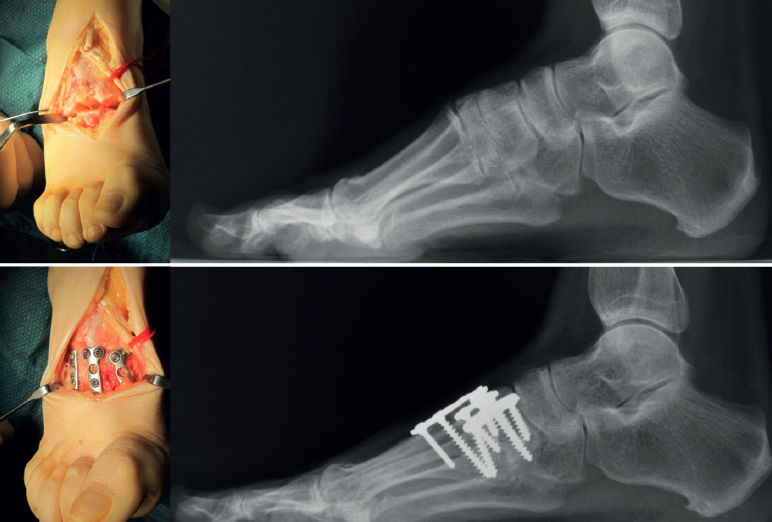

Es la indicada en el tratamiento de la deformidad moderada del mediopié. En ellas encontramos un primer radio plantar flexionado con el ápice en el mediopié (Figura 2).

Figura 3. Ejemplo de deformidad de tipo pie cavo con ápex localizado en el mediotarsiano. Se realiza una técnica de Japas asociada a una osteotomía valguizante de calcáneo.